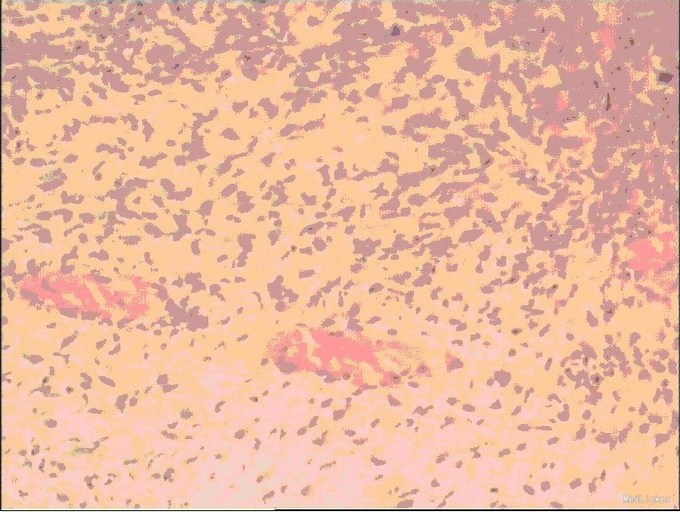

入院后,化验:血常规:白细胞:15600/mm3,嗜酸性粒细胞分数:20.3%; ESR 69 mm, CRP 176 mg/l,风湿因子:656 UI/ml,pANCA antibodies 阳性. 行肺CT:见双肺多发呈类圆形内部稍低密度影,大小不一,较大者约3.2*2.6cm(图1)。考虑肺泡出血和嗜酸性粒细胞侵润。鼻黏膜活检病理证明大量嗜酸性粒细胞侵润。根据上述,诊断为嗜酸性肉芽肿性多血管炎(EGPA,eosinphilic granulomatosis with polyangiitis)。予激素和免疫抑制剂等对症治疗。患者激素减量过程中出现咳血反复,周身及肛周出现溃疡破溃,再次与甲强龙500mg冲击后症状缓解,口腔及肛周、下肢溃烂均较前好转。进食软食一天后突然出现腹痛、发热,腹膜炎症状,查体:全腹压痛,以下腹部为重,伴有反跳痛及肌紧张。完善全腹CT检查考虑消化道穿孔(图2),EGPA并发穿孔的患者行剖腹探查,小肠穿孔修补术。术中见:腹腔小肠肠管明显扩张,多处脓苔,广泛粘连,腹腔内黄绿色渗出100ml,吸尽渗出探查,见距回盲部5cm至距TREITZ韧带150cm之间小肠多发穿孔共11处,较大者破孔3cm*3cm(图3),较小者0.4*0.4cm,予以4-0可吸收线沿肠壁横轴缝合肠壁全层及浆肌层。病理(图4):(小肠穿孔周缘)炎性肉芽组织。术后予以禁食水抗炎补液抑酸及激素治疗。术后6天因血管炎病情反复发作,出现发热,皮肤红斑,7天出现肠瘘,予以双腔套管持续冲洗接负压吸引后逐步愈合后出院。继续风湿免疫科随诊治疗。未有再次发生消化道穿孔。

血管炎(vasculitis)是一类风湿免疫疾病,是以血管的炎症与破坏为主要病理改变的一组异质性疾病,其临床表现因受累血管的类型、大小、部位及病理特点不同而表现各异。目前主要根据受累血管的大小对血管炎进行了命名和定义(Chapel Hill会议关于系统性血管炎的命名及其定义)。分为三类。第一类大血管的血管炎分为巨细胞动脉炎和大动脉炎,第二类为中等大小血管的血管炎分为结节性多动脉炎和川崎病,第三类为小血管的血管炎,曾经分为韦格纳肉芽肿(Wegener’s granulomatosis ,WG),变应性肉芽肿性血管炎(Churg-Strauss syndrome,CSS),显微镜下多血管炎,现在新的分类统称为嗜酸性肉芽肿性多血管炎。 嗜酸性肉芽肿性多血管炎,是以过敏性哮喘。嗜酸性粒细胞增多、发热和全身性肉芽肿血管炎为特征的疾病,其病理特点是坏死性血管炎,组织中嗜酸性粒细胞侵润和结缔组织肉芽肿形成。此外,系统性红斑狼疮(systemic lupus erythematosus, SLE)、类风湿关节炎、肿瘤、感染,药物等也常出现血管炎,为继发性血管炎。 血管炎累及全身多个脏器及器官,可同时合并有肺部疾患,肾功能不全,消化道缺血溃疡等。消化道受累常见于EGPA,表现为嗜酸性粒细胞性胃肠炎,以腹痛,腹泻及消化道出血常见,嗜酸性粒细胞还可侵犯浆膜引起腹膜炎。变应性肉芽肿性血管炎(CSS)患者中几乎31%消化道受累,这是已知的预后不佳的因素之一。其中小肠受累占53.5%,大肠受累占29.11%,胃十二指肠受累占16.6%,胰腺炎和胆囊炎发生率为6.3%。死亡率是11.9%。 尽管在CSS患者中,消化道溃疡性病变是常见的,但溃疡穿孔是相对罕见的,仅有有限数量的病例被报道过。 活动期血管炎导致消化道穿孔的原因分析是由于胃肠道的小血管炎和血栓形成造成缺血所致。小肠是最常发生的部位。EGPA病变的典型的病理改变为:组织及血管壁大量的嗜酸性粒细胞浸润,血管周围的肉芽肿形成以及节段性纤维素样坏死性血管炎。另一方面,血管炎的治疗方案主要是激素治疗,合并免疫抑制剂。病情加重时予以免疫球蛋白冲击治疗或行血浆置换。病程长,易反复,需要长期大剂量的激素,本身也带来多种并发症。免疫抑制剂和小肠穿孔在血管炎的病程中关系并不清楚。但研究显示免疫抑制治疗,尤其适用皮质激素类,可能在小肠穿孔的病程中发挥作用。但有时临床也很难鉴别,小肠穿孔是由血管炎本身导致,还是高剂量的免疫抑制剂造成的。 血管炎患者合并消化道穿孔的治疗上,在非病情活动期的患者,急腹症常与风湿免疫性疾病无关,恰当的手术是合适的,早期手术有较好的预后。而活动期血管炎的消化道穿孔患者临床特点可能比较复杂。需要指出的是血管炎可累及全身多个系统,患者一般情况差,长期服用激素及免疫抑制剂,糖皮质激素可抑制机体的免疫功能,且无抗菌作用,长期应用常可诱发感染或加重感染,而且用糖皮质激素时患者往往自我感觉良好,掩盖感染发展的症状,以致腹膜刺激征常不典型。该患者无明显发热,穿孔后都有腹痛加重剧烈的主诉,查体板状腹并不明显,无全腹腹肌紧张,但穿孔处的肠管的腹膜炎很明确。在临床上,如果遇到血管炎活动期,大量运用激素的患者突发腹痛的主诉时,不要漏诊穿孔的可能性。 活动期血管炎并发消化道穿孔的治疗。目前,临床上并无统一定论和治疗策略。血管炎本身无有效根治疗法,对于并发消化道穿孔的患者手术切除局部并未改变血管炎本身的自然病程。激素,免疫抑制剂等虽可减轻症状,但减量或停药后易复发,而且大量激素对手术不利,易诱发或加重溃疡,在治疗上存在矛盾。因此目前治疗主要为综合治疗,预防复发。 对于血管炎导致的消化道穿孔,有医生倾向于保守治疗,继续系统用药,认为血管炎导致的消化道穿孔,病因源自自身免疫性疾病,外科治疗属于有创治疗,缝合的肠管可能不愈合,仍不能控制病情的发展,可能有再发穿孔的危险。建议继续系统用药,控制原发病,达到穿孔自愈。目前消化道穿孔后的外科治疗仍是经验性治疗,文献报道手术治疗后极易复发。外科手术治疗需慎重。坚决杜绝因误诊而实施的相关手术,为降低术后并发症发生率,应尽量避免在急性期进行外科手术治疗。当然,若发生消化道穿孔、出血等并发症,病死率极高,需及早诊断并急诊手术治疗。另也有文献报道切除范围与术后复发无明显关联,因为多数肠道损害多可自行恢复或在药物治疗下好转。 对于活动期血管炎临床诊断明确的消化道穿孔患者,我们倾向于积极外科干预,手术治疗。我们认为,消化道穿孔虽然为自身免疫性疾患,但已然形成的穿孔通过内科保守治疗,即使病情控制,也很难自行穿孔愈合,需要积极的外科手术干预。手术方式选择:一是行消化道穿孔修补术,二是行肠切除肠吻合术。多处穿孔患者如累及肠管范围过大,考虑切除肠管后出现短肠综合征,可予以一一修补,但术后肠瘘的风险加大。对于单发的穿孔,破口巨大,周围肠管只要无明确的缺血坏死表现,可行肠切除肠吻合术。该患者穿孔处达